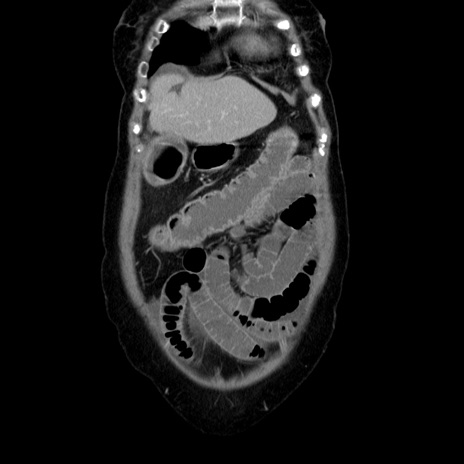

症例5(冠状断像)

【症例】70歳代女性

【主訴】お腹が張る

【現病歴】1週間くらい前から腹部膨満の自覚あり。昨日夜から増悪したため、本日救急外来受診。

【身体所見】意識清明、BT 36.5℃、BP 165/106mmHg、HR 80bpm、SpO2 98%、腹部:膨満、軟、自発痛・圧痛なし、触診にて不快感あり、腸蠕動音:減弱

【データ】WBC 12600、CRP 1.04